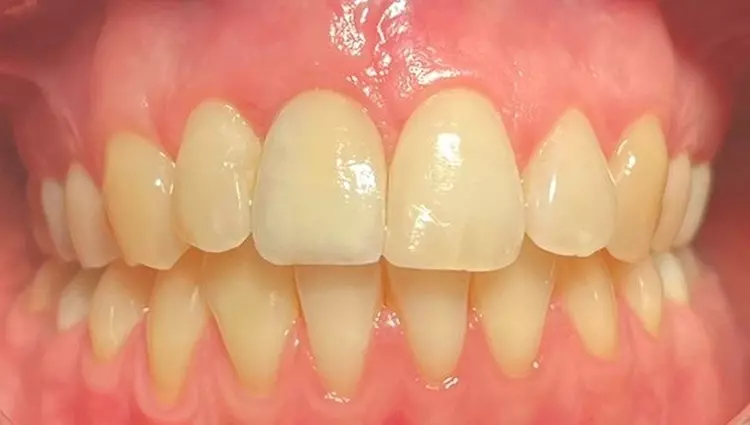

Durch den intraoperativ wiederhergestellten Alveolarkamm und die damit gestützte keratinisierte Gingiva konnte ein natürliches Emergenzprofil wiederhergestellt werden, unter Erhaltung der Interdentalpapillen. Dies zeigte sich auch bei der radiologischen und klinischen Kontrolluntersuchung nach Eingliederung des Zahnersatzes (Abb. 15 und 16).